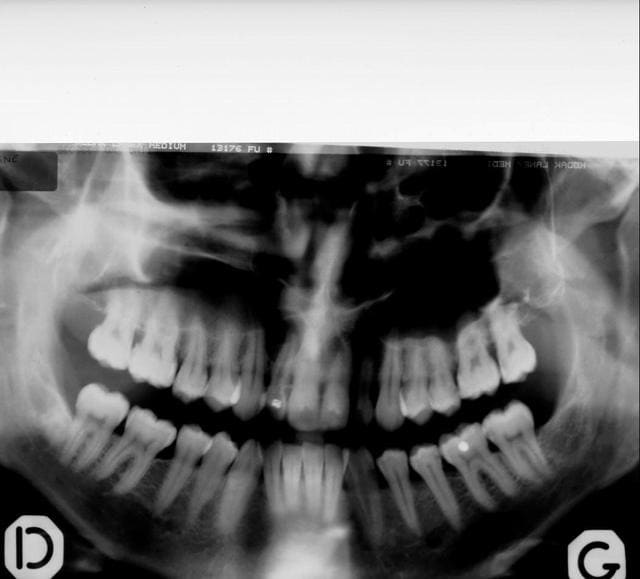

pano....youpie...scan...et là je crois qu'on décroche le ponpon...

super sinus...bien sûr la dent est condamnée...mais vous feriez quoi pour avoir une chance de planter dans quelques mois...ou du moins éviter un "énorme" défaut osseux qui sera difficilement gérable d'un point de vue esthétique...???

t'as vu la taille du kyste??? il va jusqu'au sinus et se prolonge derrière la 11...la 12 ne tiens que par son ligament palatin...

Désolé, mais la qualité de la deuxième pano est tout aussi mauvaise, tout au moins à l'écran de mon ordi : on ne voit que tu noir partout

un ptit zoom sur la pano...en renforçant le contraste...